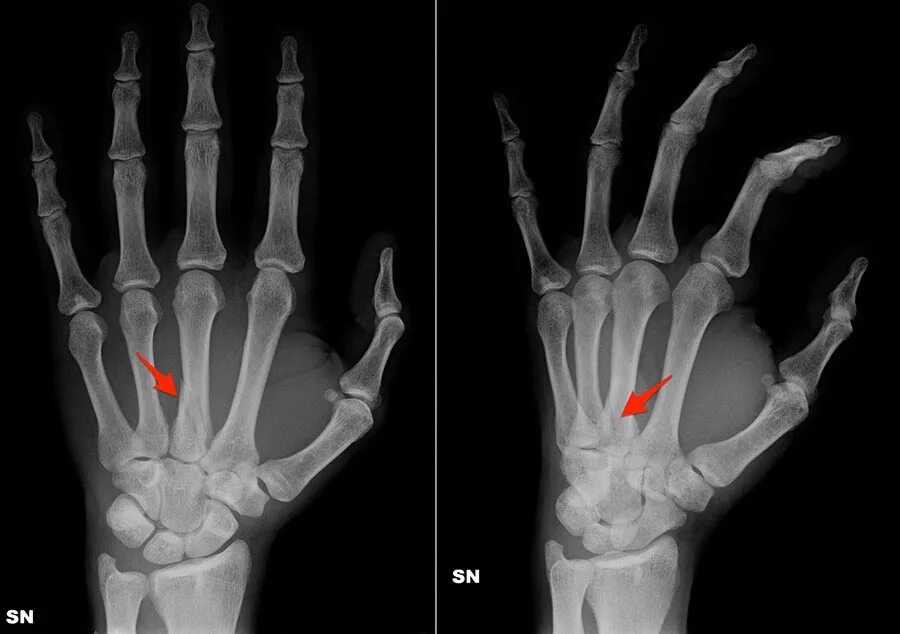

Как определить перелом руки